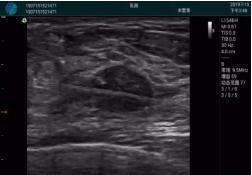

抽吸旋切后再進(jìn)行超聲復(fù)查,原腫塊區(qū)域未見殘留組織及出血

M20查看:囊內(nèi)回聲均勻,邊界清晰,囊壁光滑

M20引導(dǎo)抽吸術(shù)后囊腫消失,原區(qū)域空腔形成,脂肪層與腺體層架構(gòu)發(fā)生改變